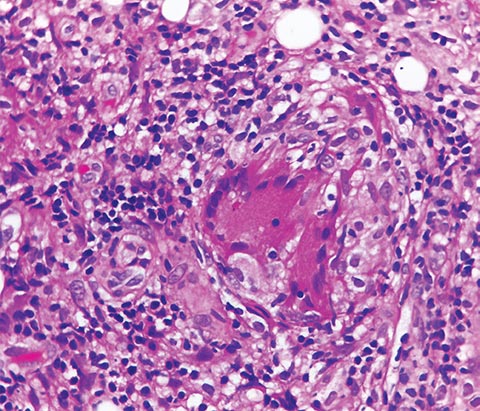

La muerte celular es la forma natural para la renovación y la reparación tisular. Se reconocían dos grandes tipos de muerte, la necrosis y la apoptosis; en la actualidad, a estas se les suman la autofagia y la ‘netosis’. La necrosis está dada por el daño de la membrana celular y la liberación del contenido citoplasmático al espacio extracelular, lo que produce inflamación y daño del tejido circundante. Es causada por agentes nocivos y trauma. La apoptosis es la consecuencia de un programa de activación de las denominadas caspasas, que lleva finalmente a la condensación de la cromatina y a la fragmentación del material nuclear, teniendo como resultado la conformación de cuerpos apoptósicos que deben ser removidos por la acción de las células fagocíticas. La falla en la remoción de los cuerpos apoptósicos se ha descrito en enfermedades como el lupus eritematoso sistémico, con importantes efectos proinflamatorios.